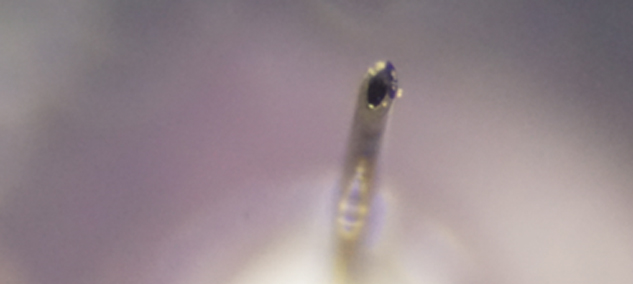

注射針の拡大写真

外径は33Gでは0.26mmでしたが35Gでは0.23mmとなっております。内径は0.11mmと、33G、35G両方変わらないのです。

外径が細くなったからといって注入圧が強くなったりということはないのです。

また、35Gは9°という鋭角な刃面加工と、シリコンコーティングにより痛みの少ない注射が

可能です。

刺通抵抗値は0.445から0.375と15%以上も低下しているようなので、その点も痛みを感じにくくなる点です。